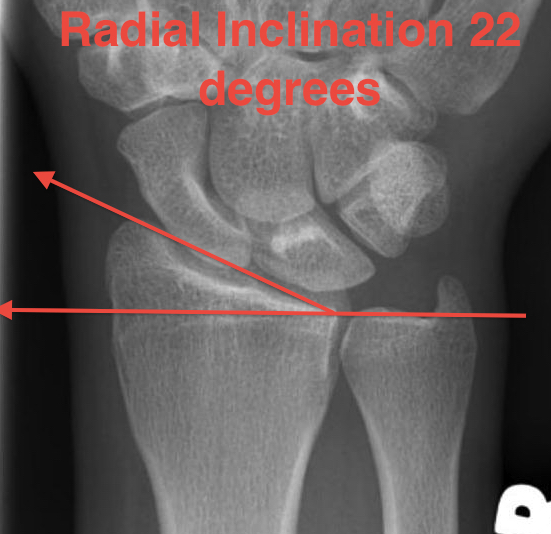

Distal Radius Angles

- radial inclination 22°

4. Radial inclination < 15o